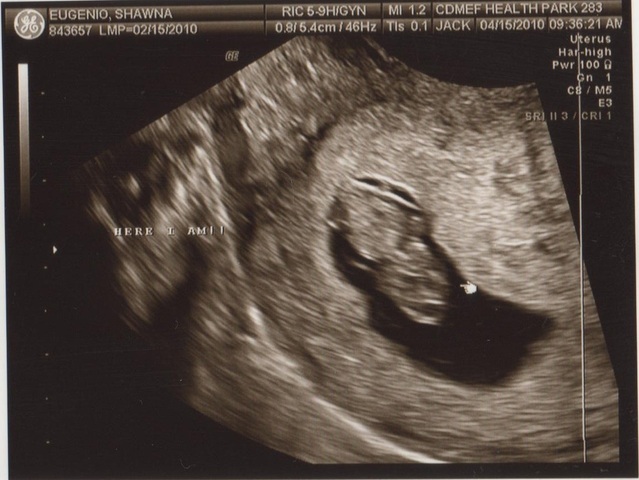

• 12 weeks

12 weeks

The most dramatic development this week: reflexes. Your baby's fingers will soon begin to open and close, his toes will curl, his eye muscles will clench, and his mouth will make sucking movements. In fact, if you prod your abdomen, your baby will squirm in response, although you won't be able to feel it.